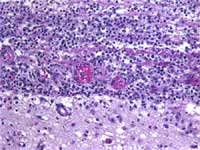

Figure 2: H & E stain shows

acute and chronic inflammation along

the leptomeninges (upper half) of

the brain (lower half)

The diagnosis of meningitis was confirmed. The leptomeninges showed acute inflammation (Figure 2). The cecum was focally necrotic and the wall was markedly thinned (Figure 3). The liver showed centrilobular necrosis (Figure 4).